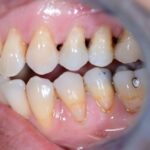

Nos réalisations : Conjointe

Céramique sur Zircone

La zircone présente une très grande résistance à la flexion (plus de 1 400 Mpa).

Translucide, elle reflète la lumière aussi naturellement que l’émail.

Biocompatible elle est garante d’une excellente intégration gingivale.